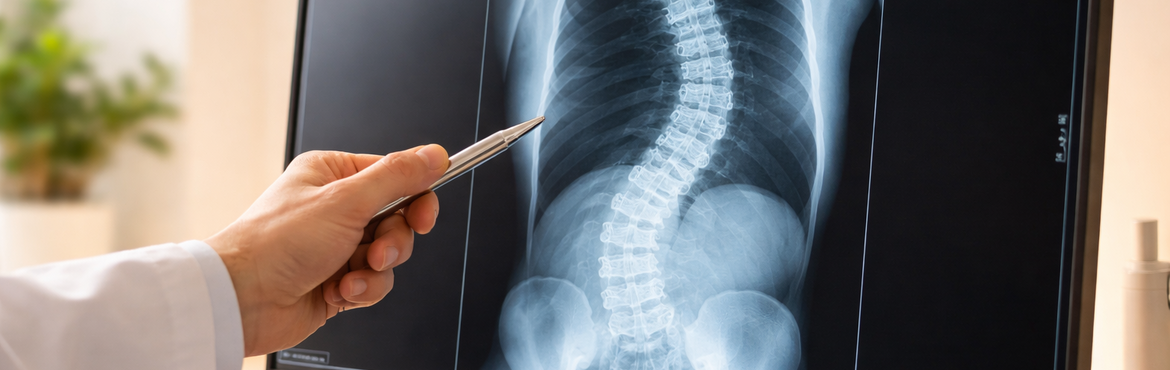

Skoliose_Korsett

Bild 1: Ein Beispiel für die Behandlung einer Skoliose im Bereich der Brust- und Lendenwirbelsäule mit einem Korsett. Die Krümmung kann fast vollständig korrigiert werden.